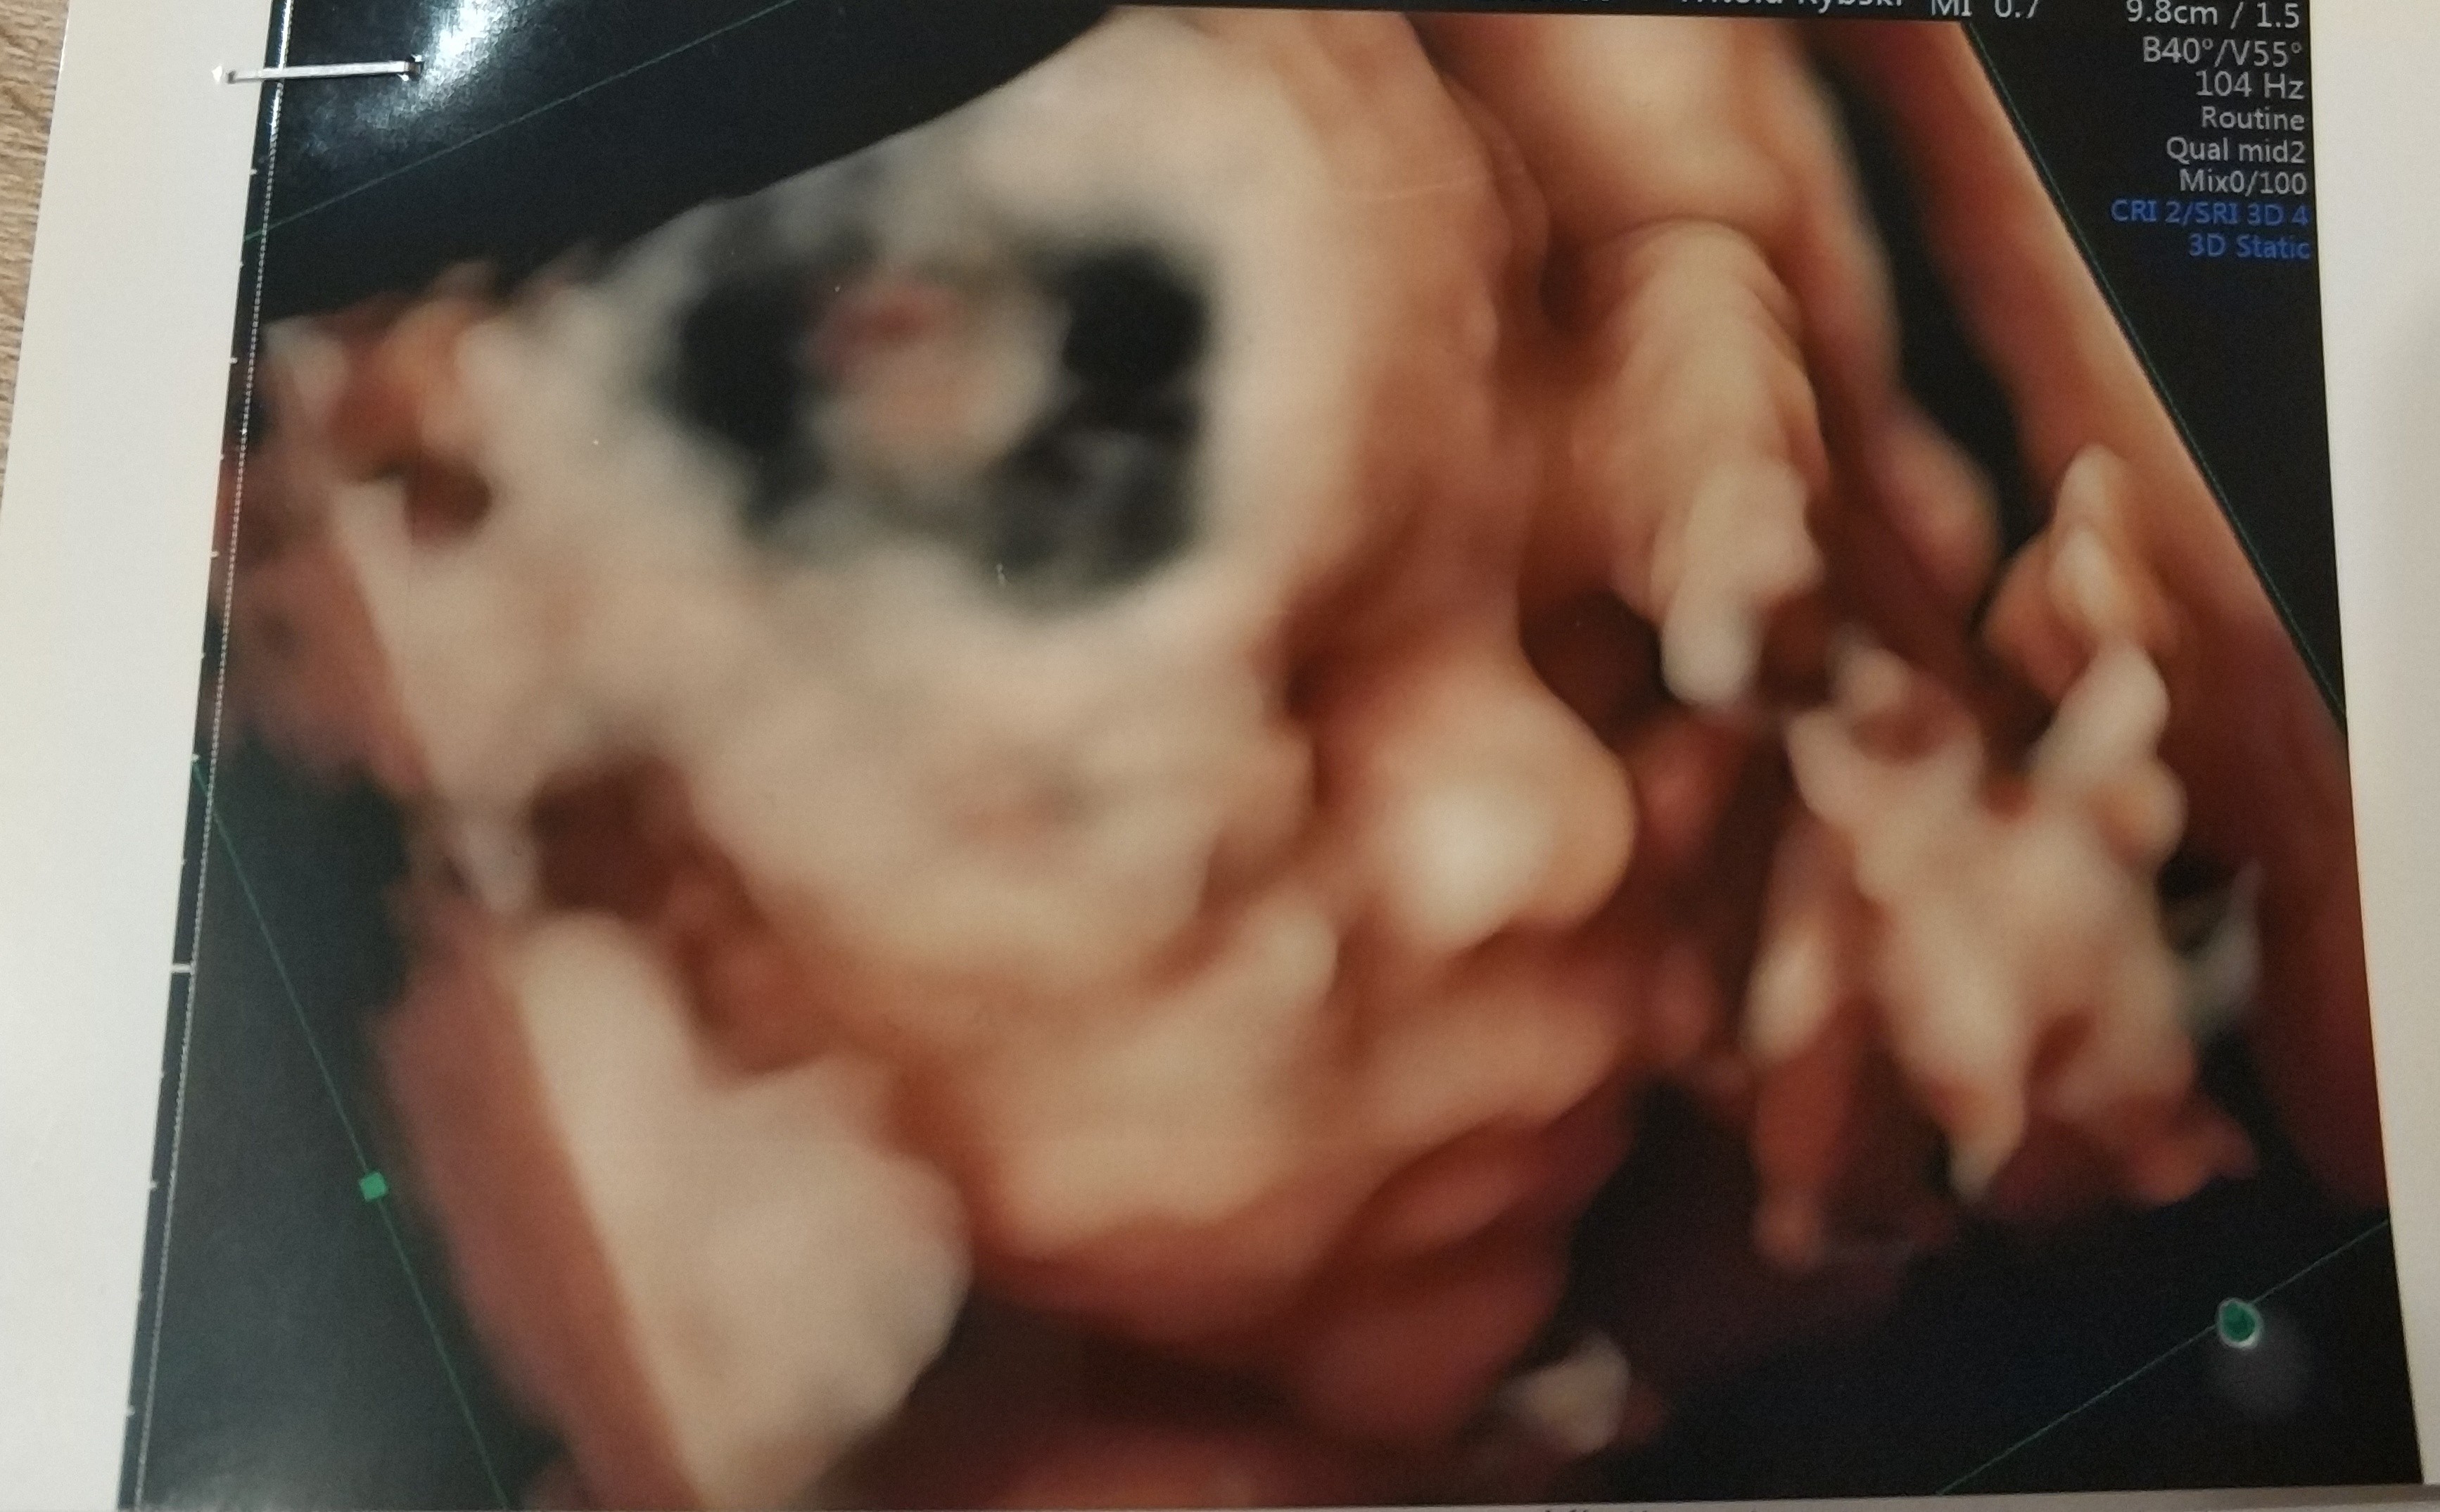

Połówkowe - wyniki

Badanie : 23t 5d

Płeć: chlopiec

Waga: 684 g

Tętno : 148

Wszystkie pomiary i narządy w porządku

Łozysko ściana przednia

Ilość wód w normie

Przepływy w normie

• IMG_20181228_221337.jpg

IMG_20181228_221337.jpg

1,2 MB · Wyświetleń: 891

Ale fajnie to zdjęcie pierwsze [emoji7] ładnie widać dzidzie

Dziękuję :) synek na tym zdjeciu wyglada identycznie jak nasza córka :)